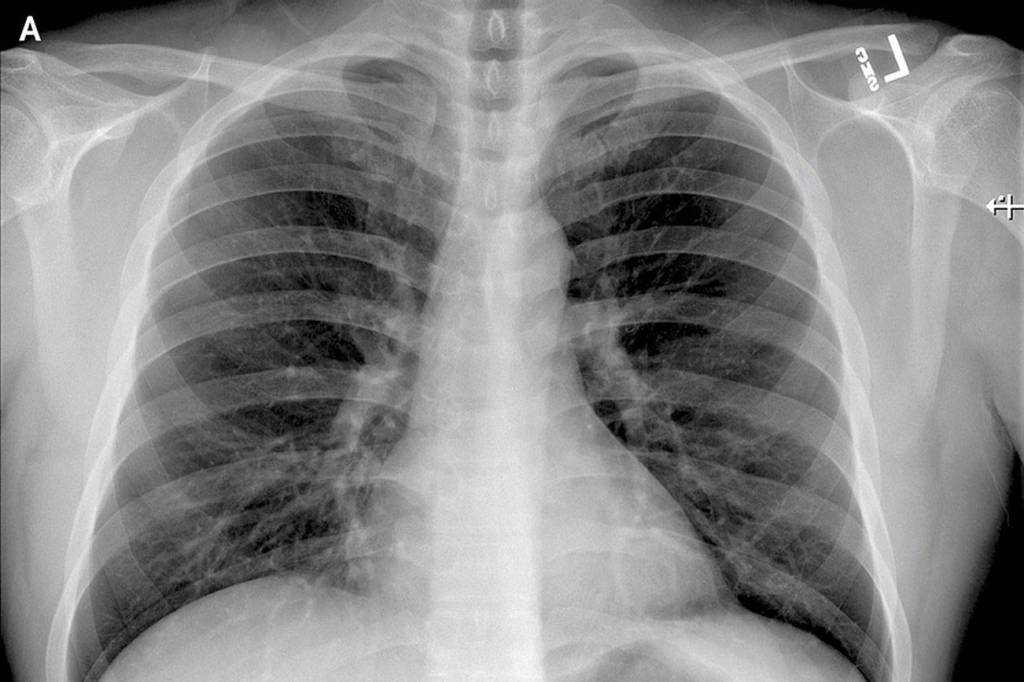

The article details the patient’s symptoms — everything from fatigue, nausea, diarrhea to a runny nose — over time and graphs his lab results. It shows X-rays of his lungs.